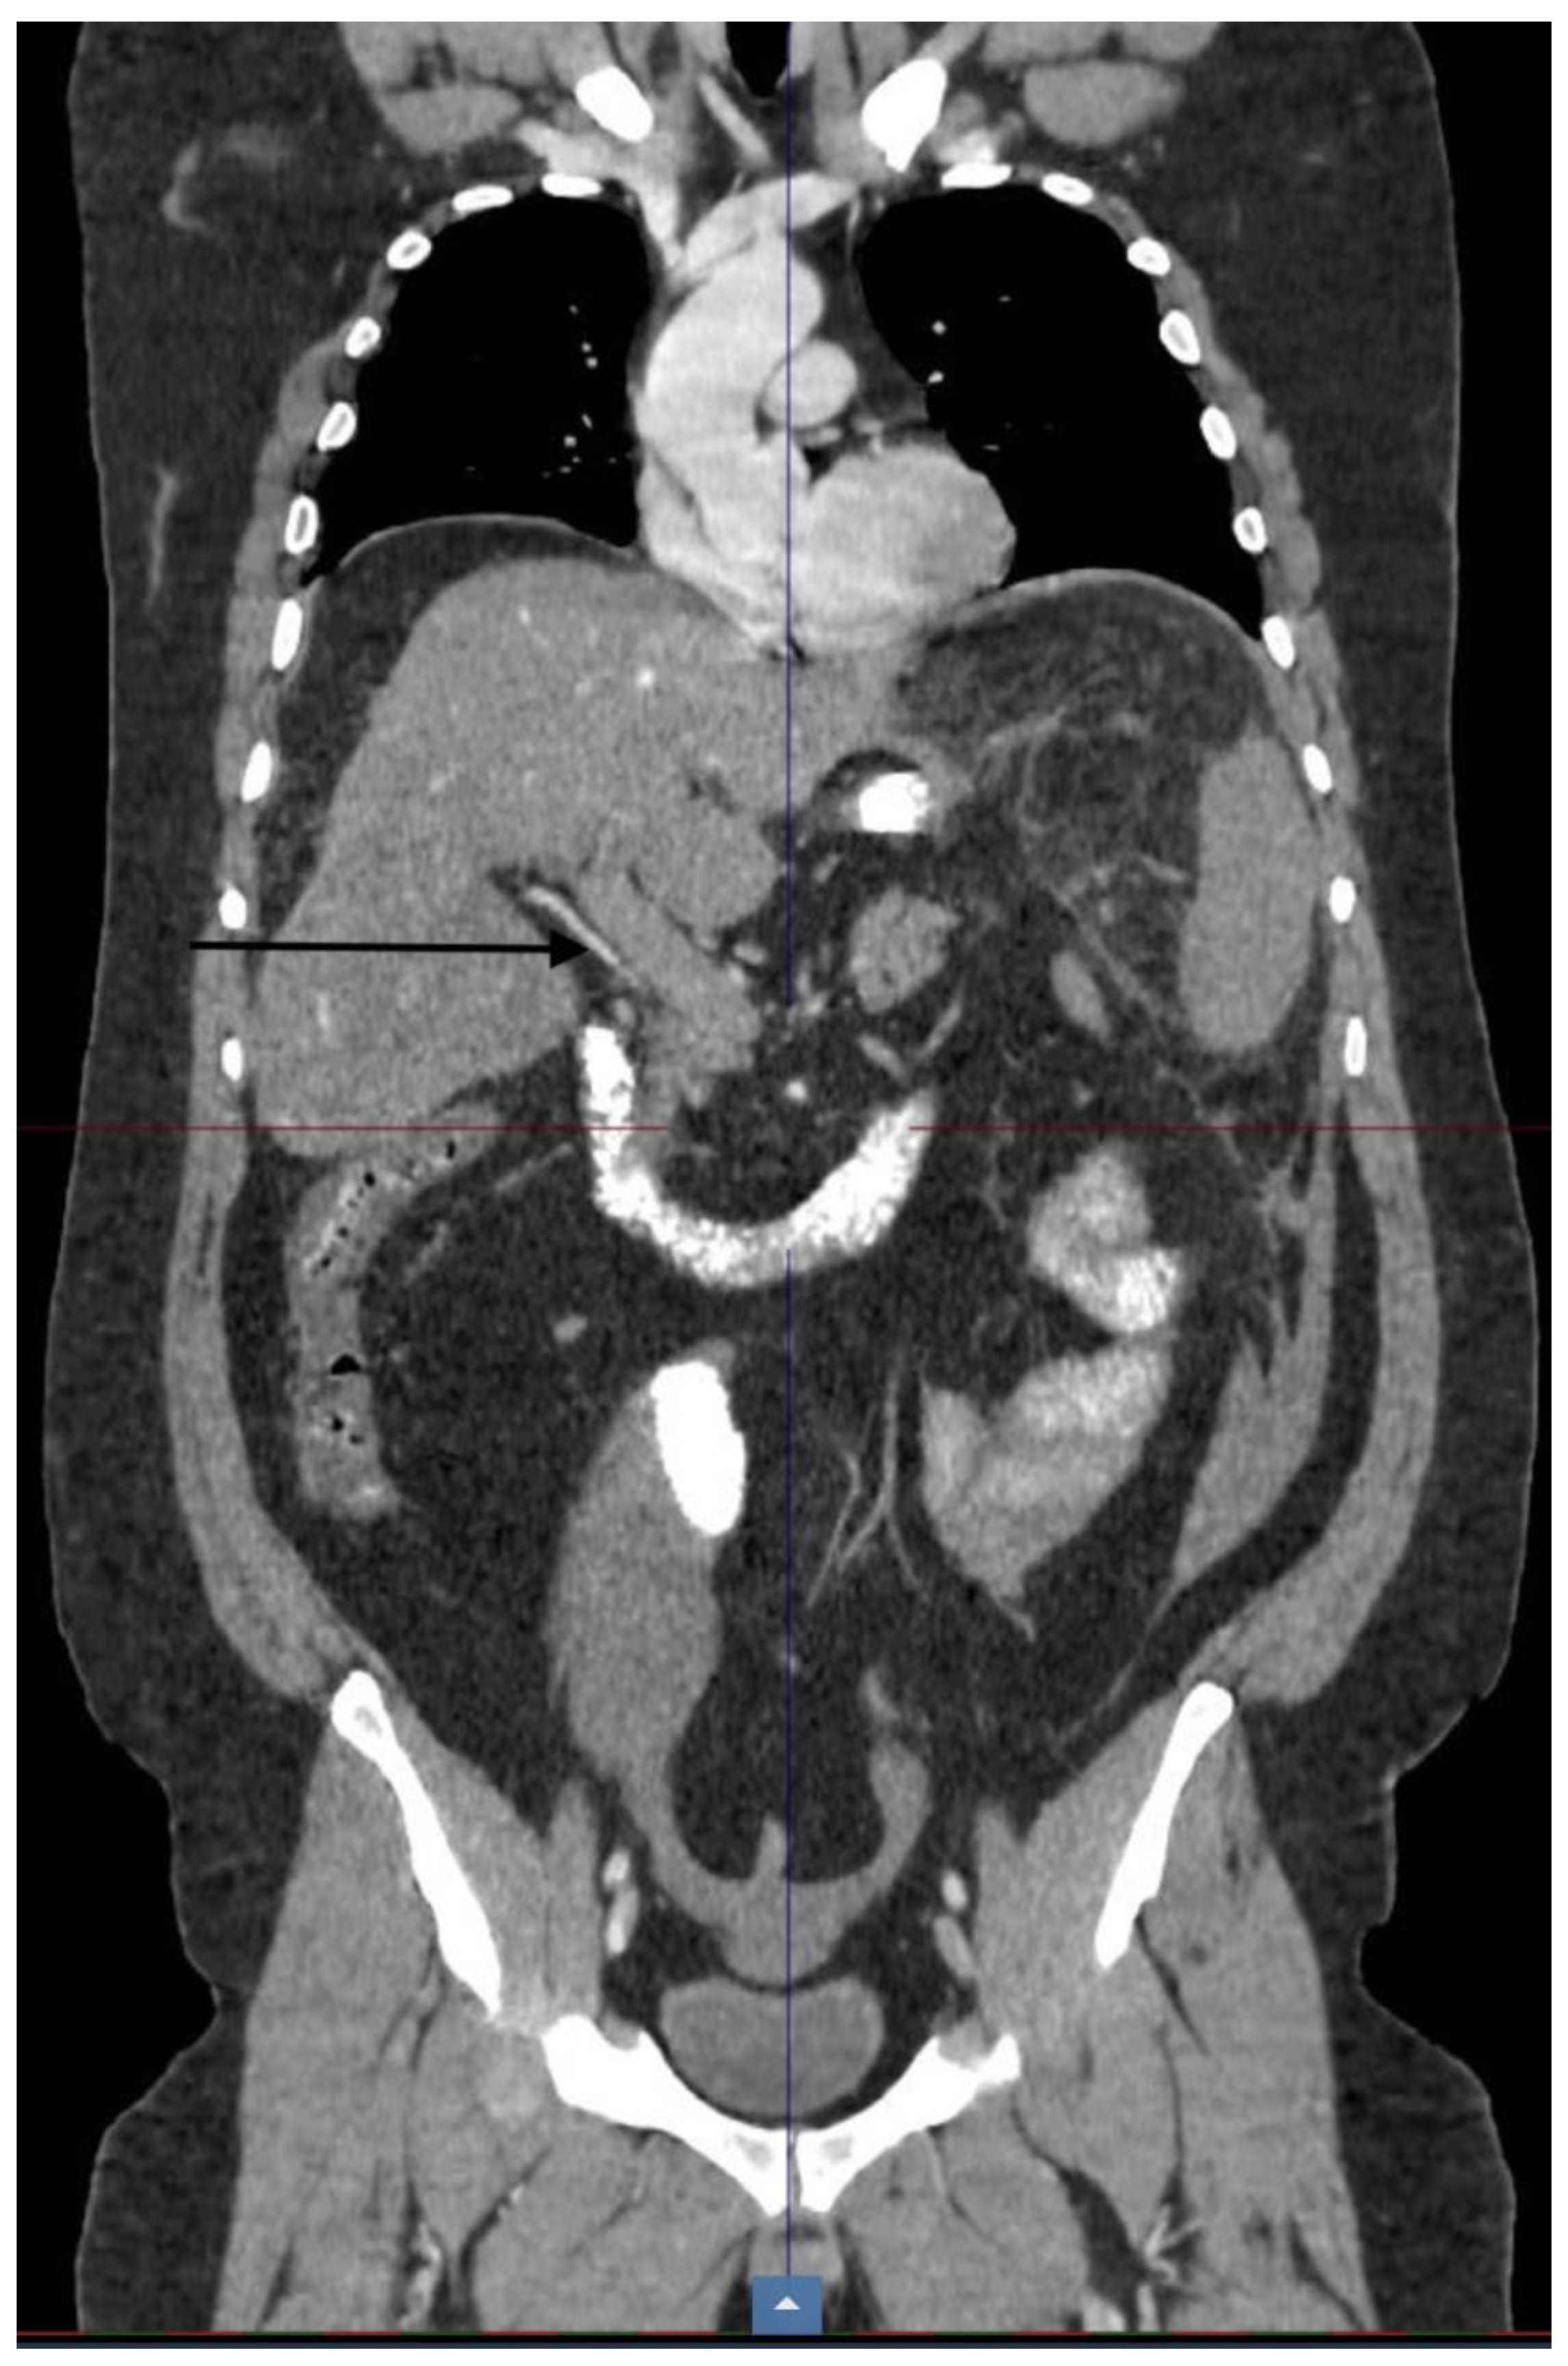

| CT scan | Nonocclusive PVT, posterior right branch, and partial superior mesenteric vein | Nonocclusive PVT, right branch, and partial superior mesenteric vein | Extensive occlusive, portal, splenic, and mesenteric thrombosis; ascites evidence of small-bowel hypoperfusion | Partial PVT |